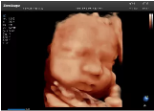

4容積探頭

積探頭是在二維圖像的基礎(chǔ)上,將連續(xù)采集的空間分布位置,經(jīng)過計(jì)算機(jī)重建算法,從而獲得完整的空間形態(tài)。

適用于:胎兒面部、脊柱和肢體等。

優(yōu)勢特點(diǎn):快速獲取、掃查連續(xù)均勻、解剖結(jié)構(gòu)顯示為容積數(shù)據(jù)、準(zhǔn)確進(jìn)行容積測量。